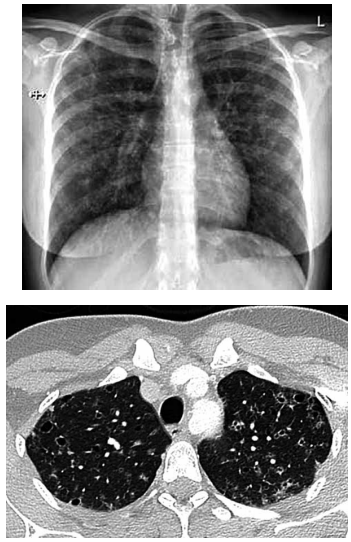

Mulher de 26 anos tem história de tosse crônica com secreção amarelada associada a dispneia ao subir escadas

rapidamente. Ela fuma trinta cigarros por dia, com histórico de 13 anos-maço. Os testes de função pulmonar

revelam (% do previsto): VEF1: 94%; capacidade vital

forçada: 94%; capacidade pulmonar total: 107%; capacidade pulmonar de difusão de monóxido de carbono

(TLCO): 57%. A radiografia e tomografia realizadas são

mostradas a seguir: O exame que mais provavelmente deve confirmar a principal hipótese diagnóstica é